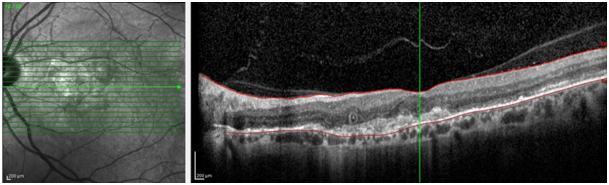

One year later, the patient presented with 20/200 BCVA without any trauma. Severe submacular hemorrhage observed on clinically and CNV was found in OCT and FFA evaluations. Hence, intravitreal ranibizumab injection switched to aflibercept therapy. Consecutive 3 injections of aflibercept were performed in one month interval. BCVA was gradually increased to 20/60, submacular hemorrhage was disappeared, macular thickness on OCT due to hemorrhage was disappeared. BCVA was remained as 20/60 even with development of slight lens opacification for one year follow-up after last intravitreal injection. In final OCT, hyporeflective spaces were resolved and legacy outer retinal tubulation was detected which can be seen in natural course of AS (Figure 2).8

Figure 2 Outer retinal tubulation, resolved hyporeflectivity and increased outer retinal hyperreflectivity in left eye’s optical coherence tomography.